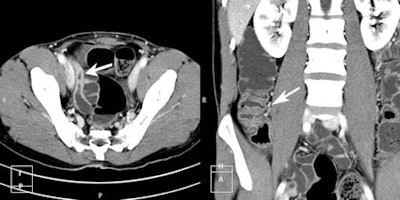

CT enteroclysis (CTE) axial and coronal images of a patient with Crohn's disease. Axial image demonstrates active inflammatory changes of terminal ileum with hyper enhancement. An added benefit of the South African authors' CTE technique is that it's possible to fill the colon with negative contrast, as can be demonstrated on the coronal image with active inflammatory changes of the cecum and ascending colon. All images courtesy of Dr. Braham van der Merwe.The small intestine is the most challenging segment of the gastrointestinal tract to examine and image because it has the largest mucosal surface. Incidence of disease is low and clinical presentation is mimicked by adjacent visceral organs with higher incidence of abnormalities, the authors explained in an in-press article posted by EJR on 8 May 2013. Thus imaging of small-bowel disease remains poorly understood by referring clinicians and radiologists.